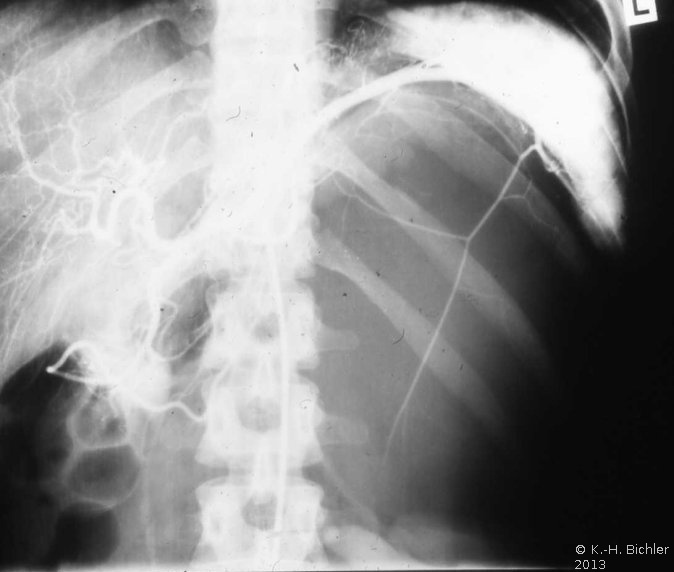

Differentialdiagnostisch muss auch an Zysten der Nebenniere gedacht werden, die zum Teil von erheblicher Größe sein können. Operative (laparoskopische) Entfernung ist bei großen, rupturgefähredeten Zysten angezeigt. Die Abbildungen dazu beispielhaft (Abbildungen 2,3).

In einem weiteren Beispiel fand sich eine 8x10 cm große Nebennierenzyste, die in der Angiographie eine deutliche Abdrängung der rechten Niere zeigt